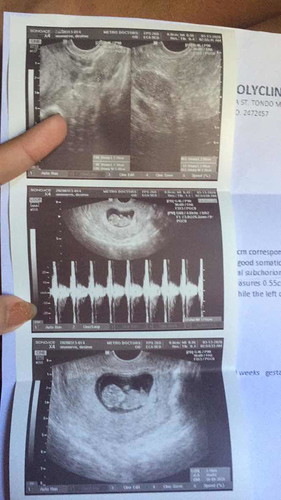

masyado akong natakot nung bigla akong dinugo pero nung malaman ko na normal baby ko sobrang saya pero nakakatakot lang na may posibility parin ako makuna